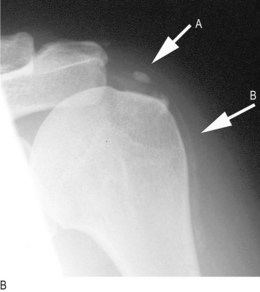

Osteoporosis is systemic skeletal loss of bone mineral density with associated microarchitectural deterioration. It is the most common cause of abnormal bone structure. The incidence increases with age, particularly in postmenopausal women (Box 14.27). In the absence of complications, osteoporosis is asymptomatic. Although any osteoporotic bone can fracture, common sites are the distal radius (Fig. 14.56), neck of femur (Fig. 14.43), proximal humerus and the spinal vertebrae. Caucasians in Europe have a lifetime risk of osteoporotic fracture of 50% in women and 20% in men.

Fig. 14.56 Colles’ fracture. (A) Clinical appearance of dinner fork deformity. (B) X-ray appearance.